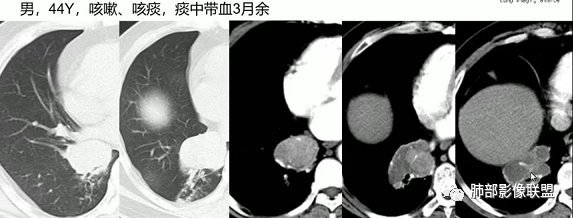

1、简要病史:老年男性,咳嗽咳痰伴痰中带血半年,既往长期吸烟史,臀部脓肿手术史。

2、实验室检查:神经元特异性抗原27.5ng/ml,鳞状细胞癌抗原0.611ng/ml,角蛋白抗原19片段3.2ng/ml,结核抗体、结核菌涂片正常,白细胞、C反应蛋白正常,其余实验室无特殊。

3、影像表现:肺气肿背景,右肺上叶后段支气管开口阻塞并见腔内软组织影轻度突向叶支气管,阻塞段以远支气管及分支扩张填塞呈指套样改变,轻度不均匀强化,外周点片影,符合阻塞性炎性表现,现有图像资料未见明确肺门纵膈淋巴结增大。

4、结合患者年龄、病史及影像表现,常规需要鉴别的疾病谱有:

①鳞癌:老年男性,长期吸烟史,支气管腔内占位有强化、指套征,周围阻塞性炎症,常规需要考虑。

②小细胞肺癌:多见于吸烟男性,周围型多见,病灶沿支气管匍行,管壁增厚,阻塞有时不彻底,典型者呈鸭蹼和腊肠样凸起,增强沼泽样强化,阻塞性肺炎相对较轻,较少肺不张。易较早转移到纵隔和肺门淋巴结,出现“娘小崽大”特征,多个淋巴结融合则呈现“冰冻纵隔”。本例病灶有类似鸭蹼样改变,加上患者长期吸烟史、NSE增高,不除外小细胞肺癌,但纵隔及肺门淋巴结肿大、融合的趋势不明显。

综上,本例考虑恶性肿瘤性病变,以鳞癌可能性大,亦不除外小细胞肺癌、粘液表皮样癌等,另外还需密切结合病史排除异物等病变可能。

右肺上叶支气管腔内鳞状细胞癌,乳头状亚型